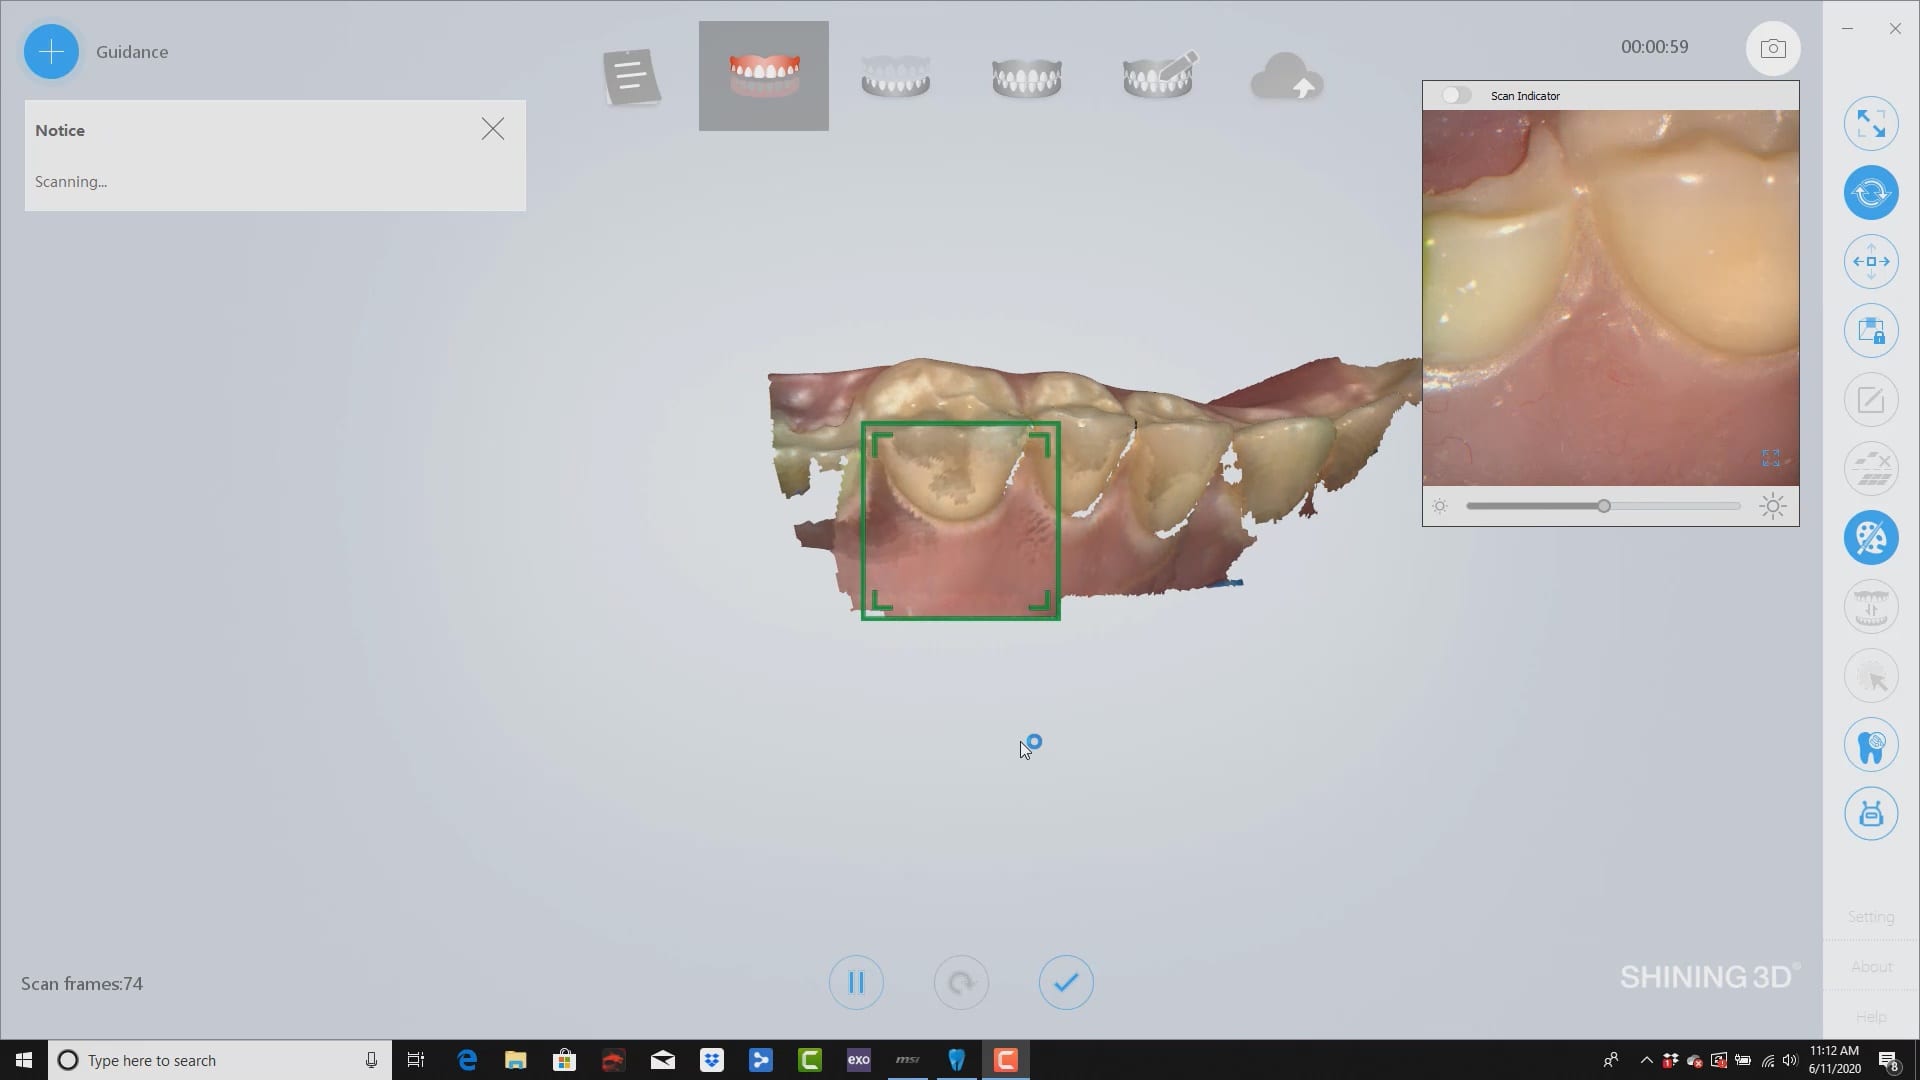

upper denture duplicated with shining 3d. only needed the occlusal and buccal surfaces as the case is for a lower overdenture over immediate extractions, on healed implants. went ahead and just duped the whole denture with the ios. very good results